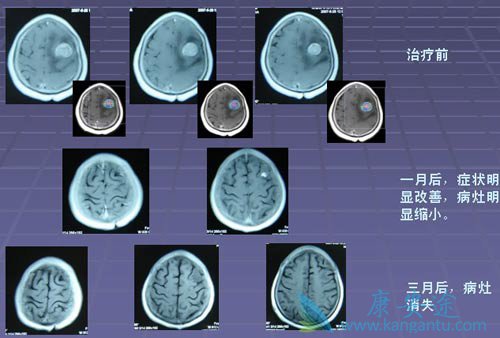

肺癌脑转移五年生存率

在大多数人的意识里,癌症就代表着绝望与死亡。但据中国工程院院士、中国医学科学院肿瘤医院孙燕教授2011年介绍:“肿瘤科医生患癌后, 80%都得到了治愈(5年生存)特别是一些发生肺癌脑转移,目前依然带瘤生存。”。而国家癌症中心全国肿瘤防治研究办公室随访至2010年年底的数据分析显示:我国全部癌症5年生存率为30.9%。

徐林友本身是肺癌医生,2011年1月自己却被查出肺癌脑转移,当时被医生判定为“很难活过100天”,如今6年过去了,仍旧活得很健康。所谓五年生存率,对于一个癌症病人来说,从临床标准来看,可以说是临床治愈了!